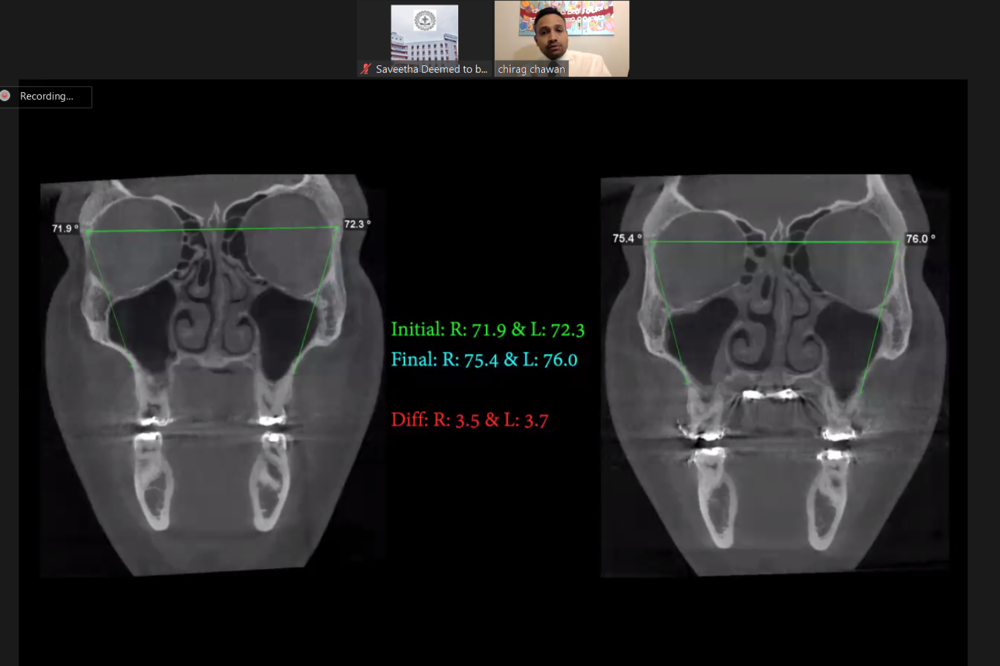

WEBINAR ON TRANSVERSE DICREPANCIES ADDRESSED WITH MARPE

Webinar on Transverse discrepancies was delivered by Dr Chirag Chawan who is an American Board certified Diplomat, UCLA alumni and practicing in Kent, USA. It was an interactive webinar attended by 80 delegates.